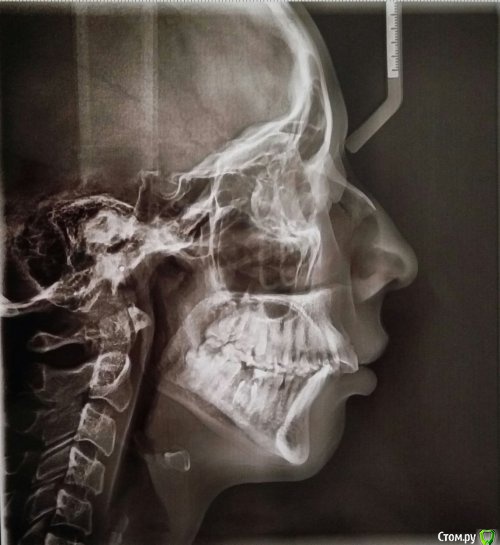

Ксения_занятый логин Опубликовано 29 марта, 2017 Автор Поделиться Опубликовано 29 марта, 2017 Прилагаю рентген Ссылка на комментарий

Brigita Опубликовано 31 марта, 2017 Поделиться Опубликовано 31 марта, 2017 по поводу Гербста - он выдвигает нижнюю челюсть вперед, в 27 лет сустав уже сформирован, на ОПТГ видно, что при выдвижении челюсти для закусок она находится в максимально переднем положении, особенно справа. Для того, чтобы определить не пострадает ли сустав от таких перемещиений - нужно сделать снимок в конструктивном прикусе, изготовить такой силиконовый сплинт, на расстояние, которое ортодонт хочет переместит челюсть и с ним уже на снимок. Посмотреть на сустав. Убедится в ложности такой идеи.Вы, возможно добьетесь какого то результата со стороны зубов, они у вас сомкнутся наконец, но заработаете очередную проблему - сустав. Ссылка на комментарий